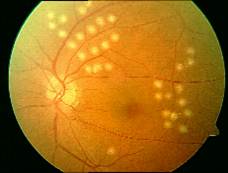

眼底病专科

常见眼病